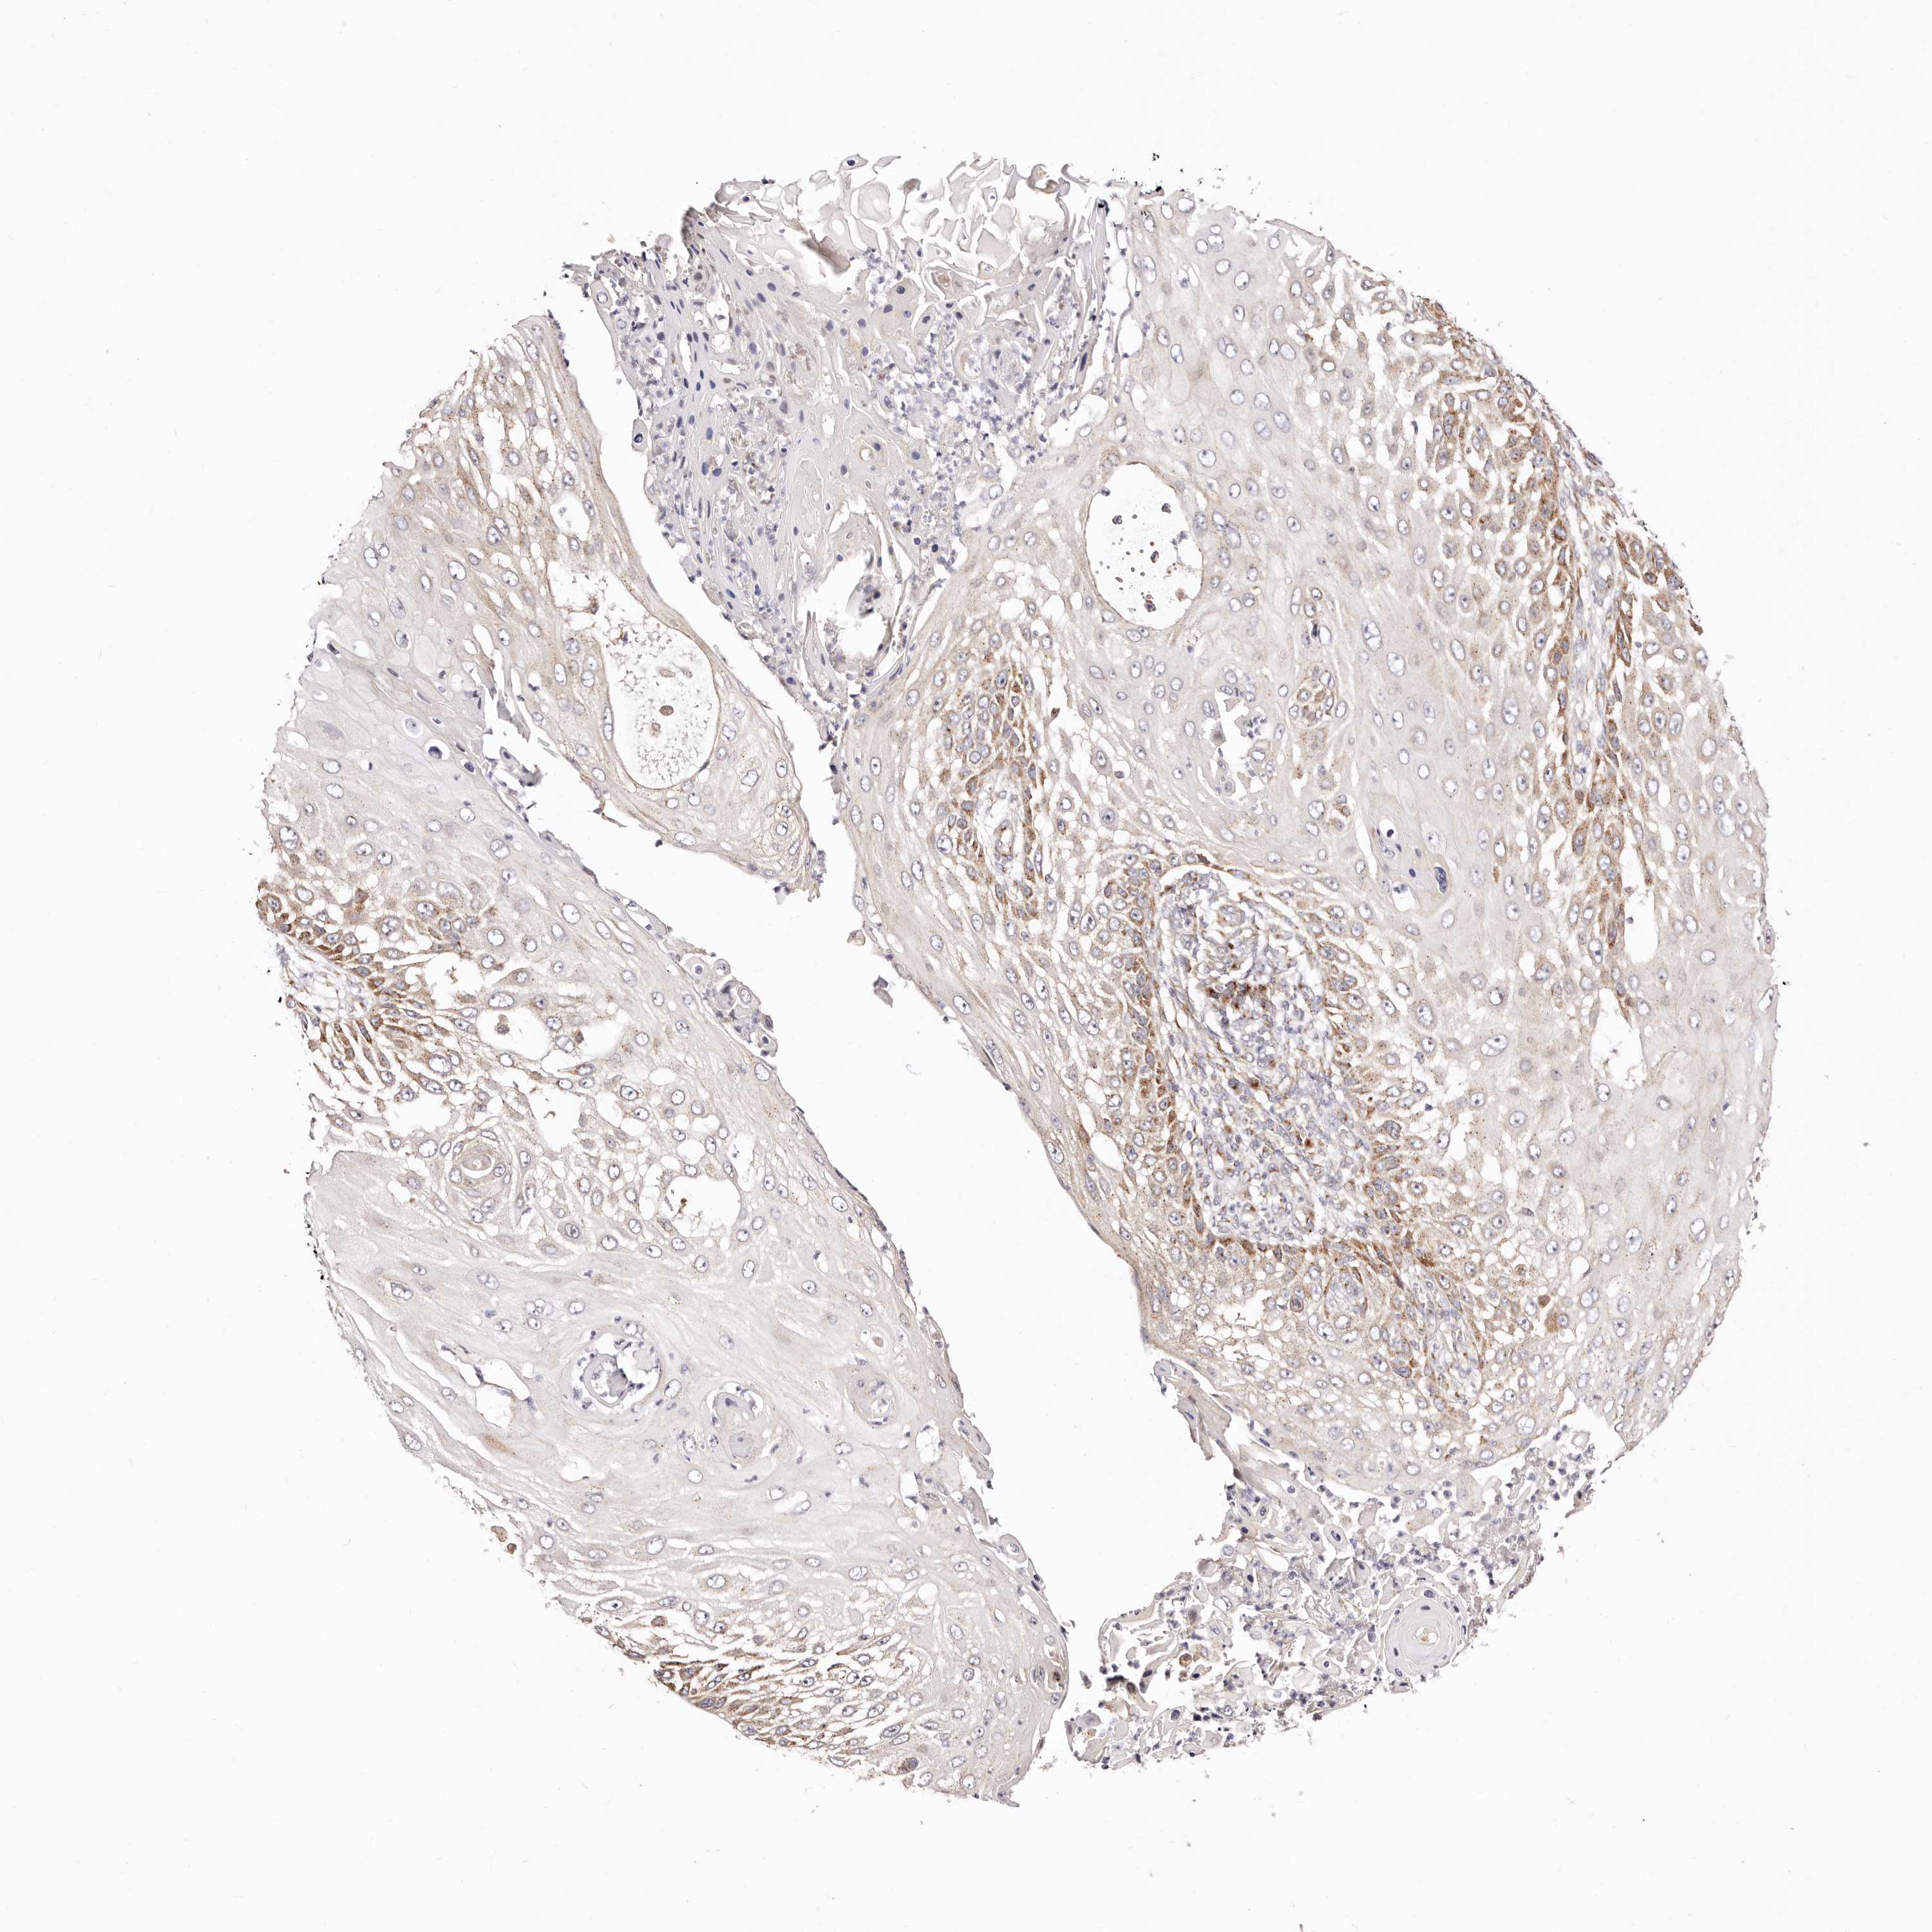

Basal cell and squamous cell cancer

SKIN CANCER - Protein expressioni

A mouse-over function shows sample information and annotation data. Click on an image to view it in a full screen mode. Samples can be filtered based on level of antibody staining by selecting one or several of the following categories: high, medium, low and not detected. The assay and annotation is described here.

Each image is clickable and will lead to virtual microscopy that enables deeper exploration of all samples and also displays staining intensity scores, fraction scores and subcellular localization as well as patient and tissue information for each sample.

Antibody HPA030262

Antibody HPA047825

Antibody CAB005184

Basal cell carcinoma

Squamous cell carcinoma, NOS

Squamous cell carcinoma, metastatic, NOS